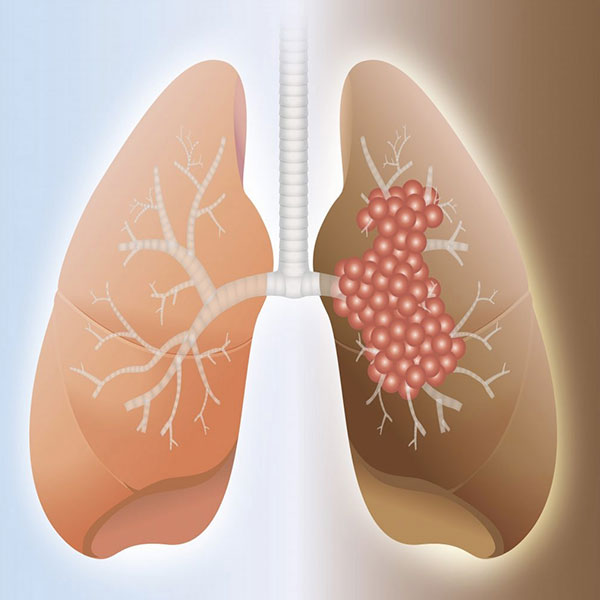

Lung Biopsy

Lung biopsy services involve extracting lung tissue for diagnostic testing, identifying conditions like cancer or infections.

Lung Fibrosis

Lung fibrosis causes lung tissue scarring, leading to breathing difficulties, persistent cough, and reduced oxygen supply over time.

Interstetial Lung Disease

Interstitial lung disease refers to a group of disorders causing scarring and inflammation in the lung's interstitial tissue.

Ideopathic Pulmonary Fibrosis

Idiopathic Pulmonary Fibrosis is a progressive lung disease causing scarring, difficulty breathing, and reduced lung function.

Lung Surgeries

Lung surgeries treat various conditions like cancer, infections, and COPD, improving lung function and overall health.